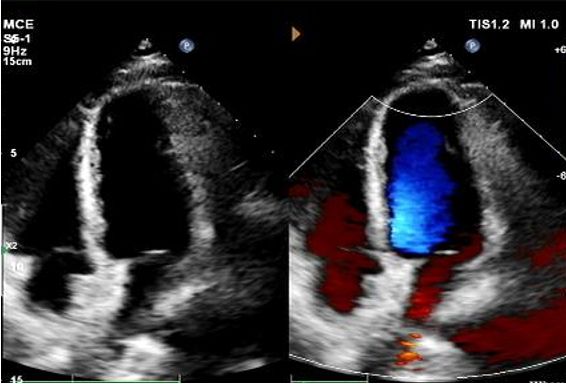

Dzień od 1 do 9 miesięcy:

Nie zaobserwowano szczątkowego bocznika.

Stopniowe zmniejszanie echogeniczności urządzenia.

Echo 1-letnie:

No visible disc structures – replaced by 8mm tissue thickening at the septal implant site.

Zero residual shunt (rest or post-Valsalva).

Potwierdzono pełną absorpcję urządzenia.